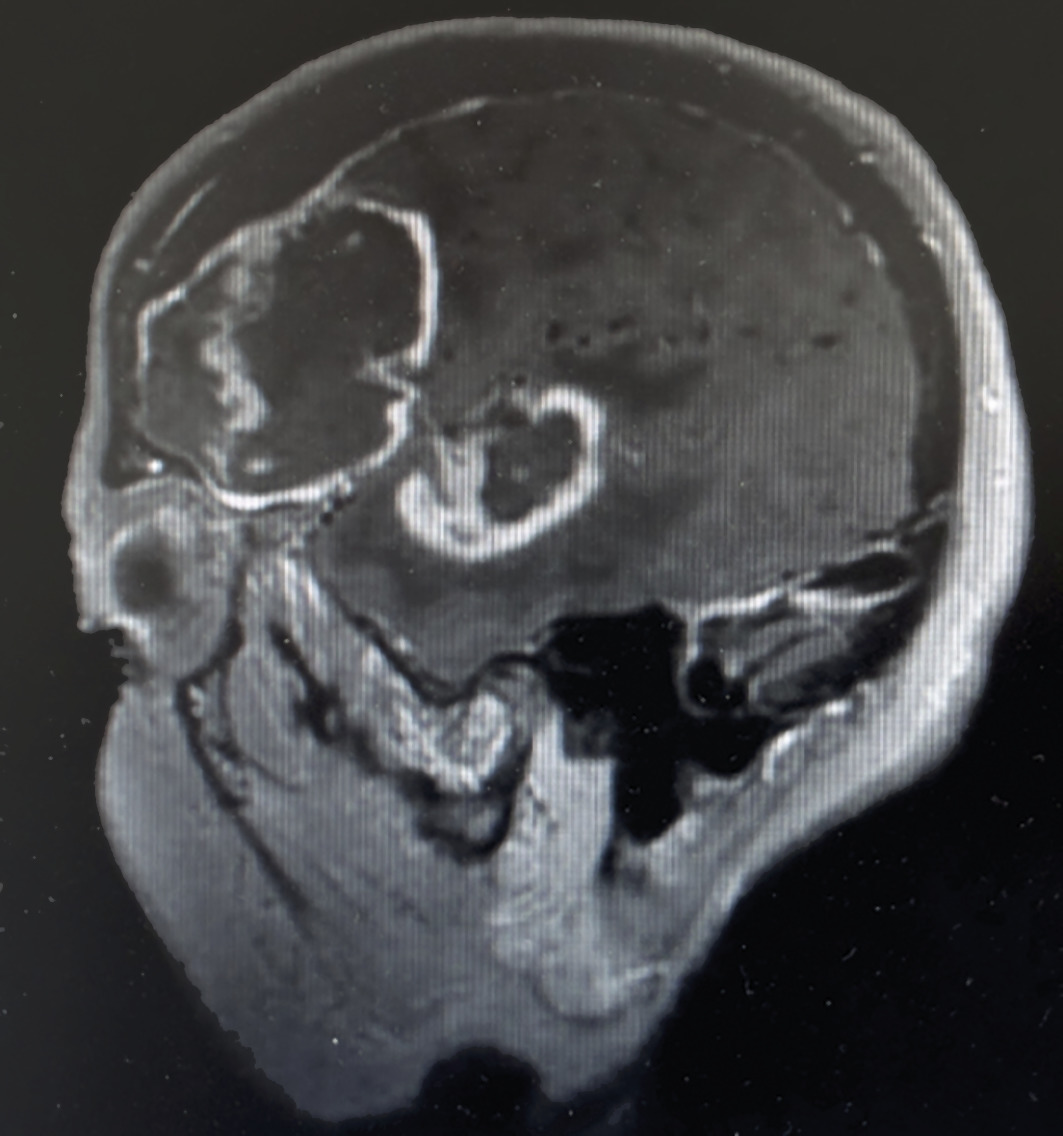

Chez les immunodéprimés (transplantés ou infectés par le VIH), les LNH sont l’un des cancers les plus fréquents. Il s’agit volontiers de formes agressives. On observe jusqu’à 10 % de LNH du SNC, avec des aspects spécifiques en cocarde, similaires à ceux retrouvés lors des toxoplasmoses (fig. 5). Le virus d’Epstein-Barr est souvent impliqué dans leur physiopathologie.